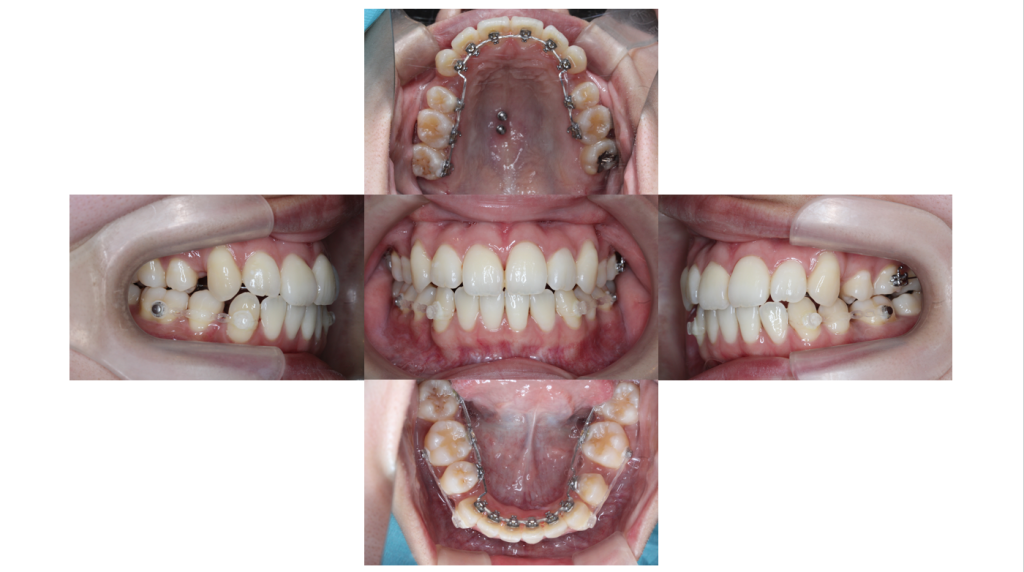

初診

上顎前突・裏側矯正の症例治療開始前の口腔内